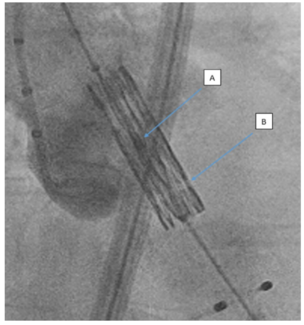

Percutaneous coronary intervention with Y-stenting of coronary bifurcation disease is not commonly undertaken. The procedural and medium-term clinical outcomes of coronary bifurcation lesions treated with the proximal to distal Y stent...